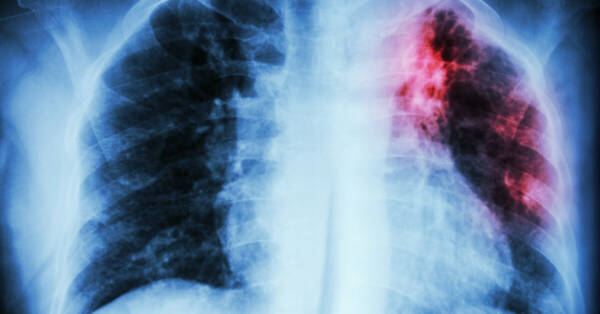

المغرب يعزز جهوده لمكافحة السل

أفادت وزارة الصحة والحماية الاجتماعية، بأن الإحصائيات الخاصة بسنة 2025 أظهرت أن 53 في المائة من حالات السل الجديدة المسجلة بالمغرب تتعلق بالأشكال خارج الرئة، وهو ما يسلط الضوء على تحدٍ صحي يستدعي مزيدًا من اليقظة والتوعية.

وأوضحت الوزارة، في بلاغ لها بمناسبة تخليد اليوم العالمي لمكافحة السل لسنة 2026، أن هذه المعطيات تبرز أهمية تعزيز الجهود في مجال التشخيص المبكر، خاصة أن هذا النوع من السل لا يزال أقل شهرة ويصعب اكتشافه مقارنة بالسل الرئوي.

وأكدت الوزارة أن تخليد هذه المناسبة، التي تنظم هذه السنة تحت شعار “السل يتجاوز الرئتين.. لنعزز الوعي بالأشكال خارج الرئة”، يشكل فرصة لتكثيف حملات التحسيس والتوعية، وتشجيع المواطنين على اللجوء المبكر إلى الخدمات الصحية عند ظهور الأعراض، إلى جانب دعم مهنيي الصحة في التعرف على هذه الأشكال المعقدة من المرض والتكفل بها بشكل مناسب.